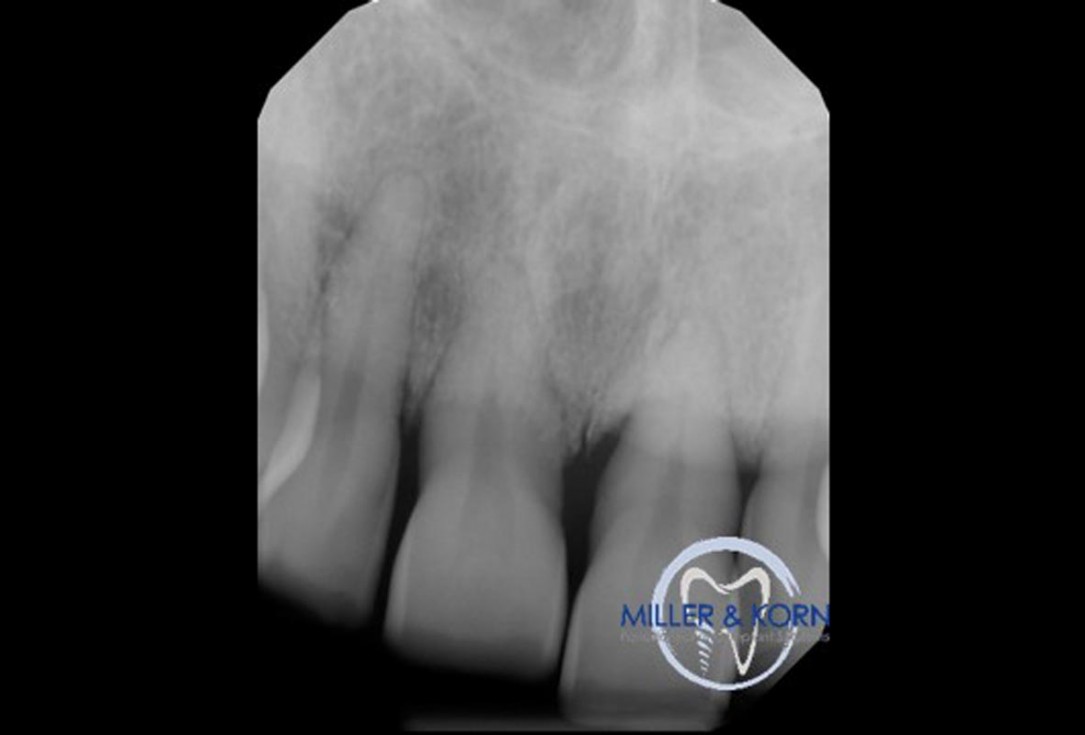

34/39 - Preoperative radiographImmediate implant placement and correction of horizontal and vertical bone loss using an allograft bone ring, cerabone® and Jason® membrane - Drs. Miller and Korn